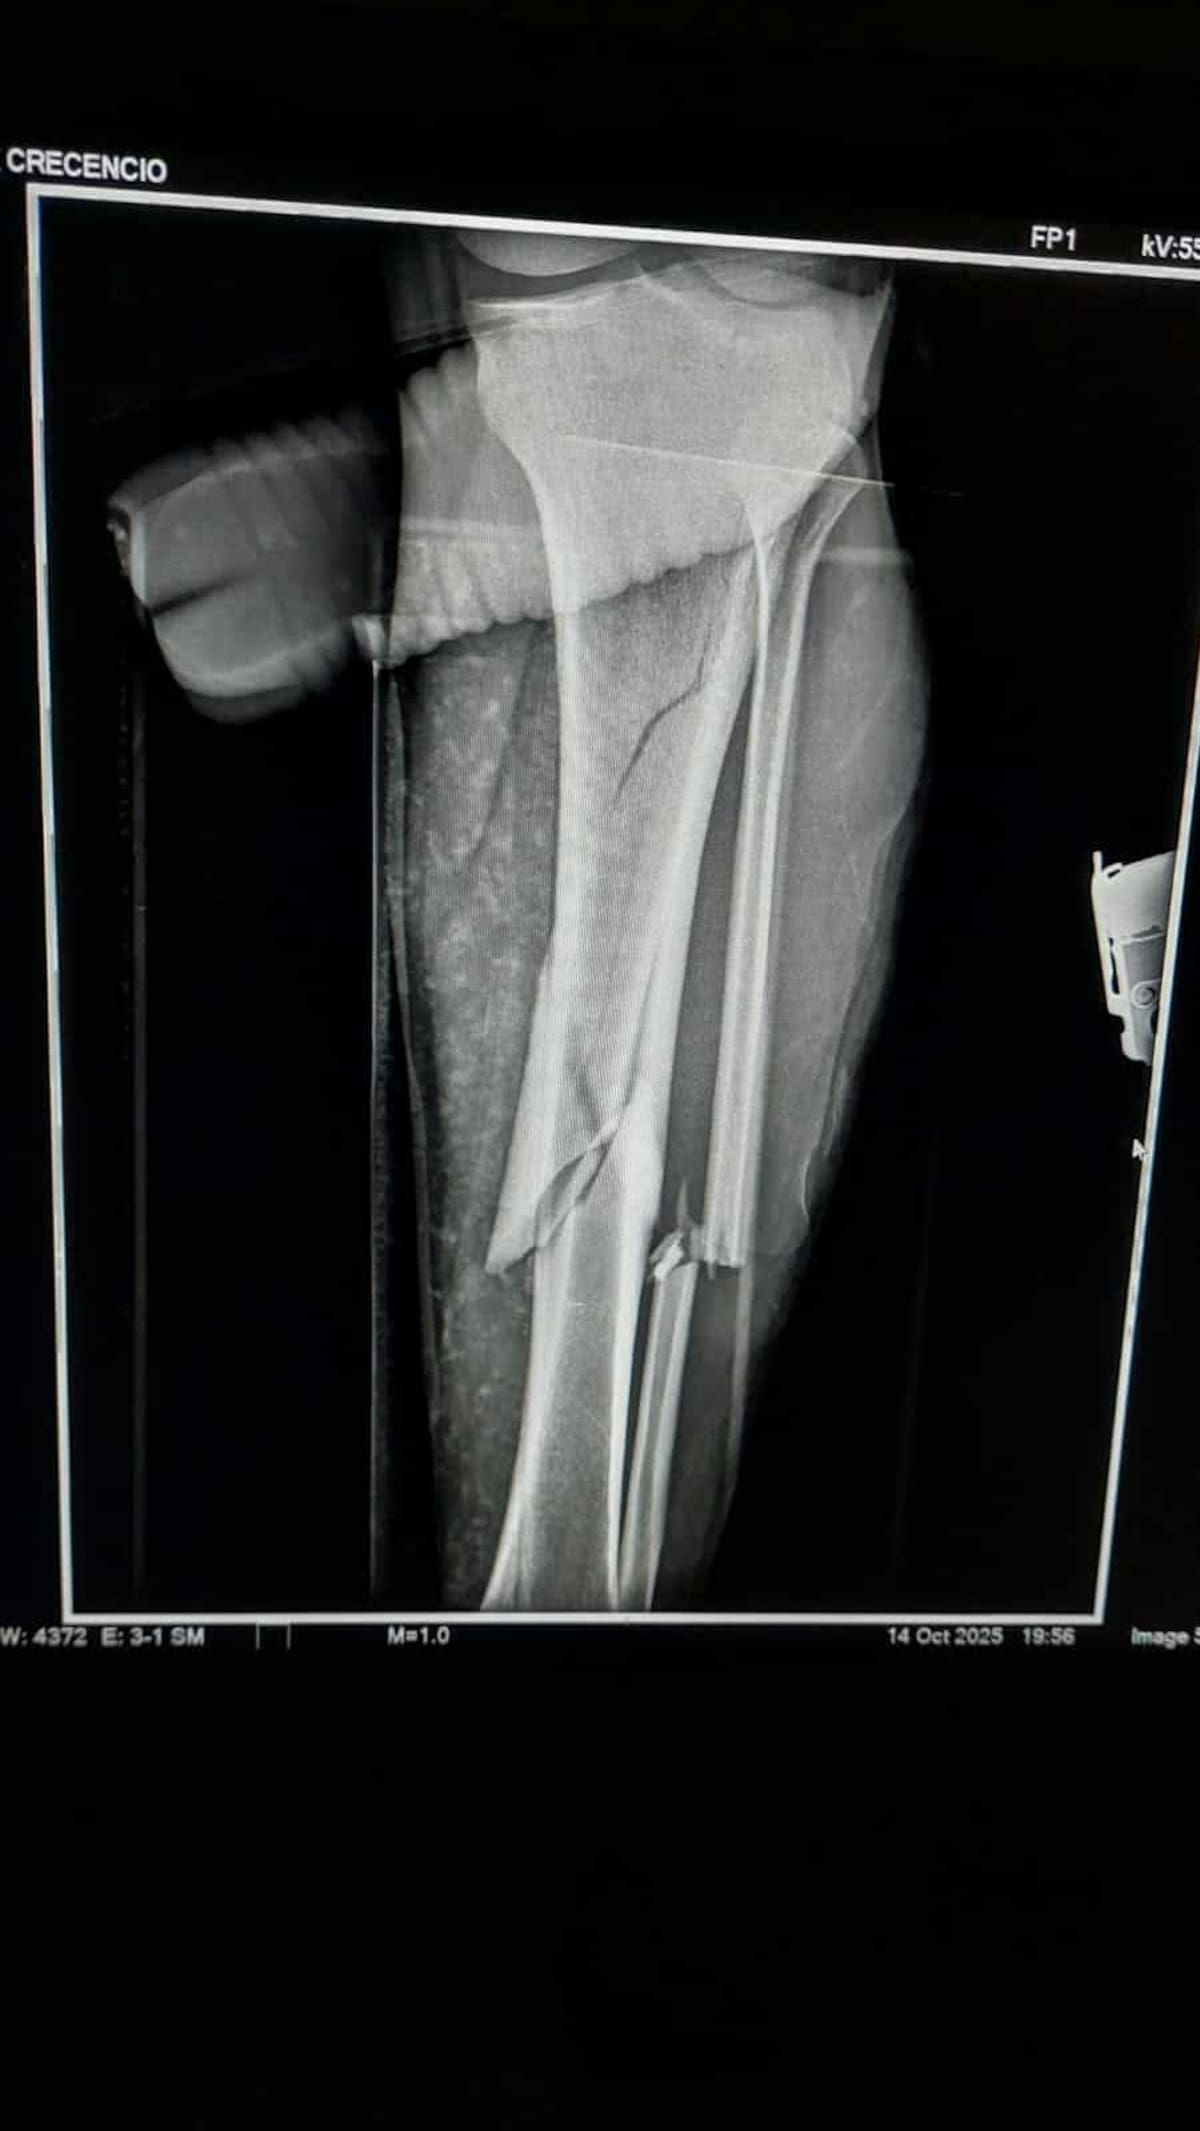

Los paramédicos reportaron que el migrante contaba con fractura no expuesta en tibia y peroné de la pierna izquierda, por lo que fue estabilizado y trasladado al hospital IMSS Bienestar, lugar en el que recibe atención médica.